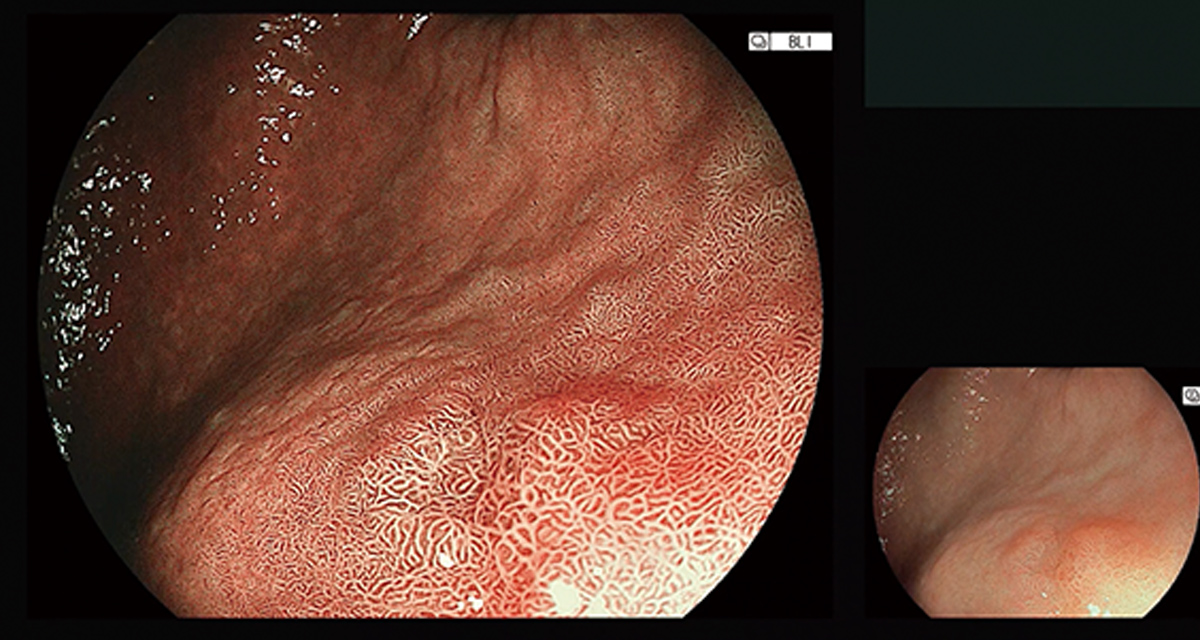

胃カメラ検査の様子

胃カメラ(胃内視鏡検査)は、口または鼻から細いカメラを入れて、のど・食道・胃・十二指腸の入口を直接見て確認する検査です。胃炎や潰瘍・ポリープなどの変化を早めに捉えやすく、必要があれば組織を少し採って詳しく調べたり、ピロリ菌感染の確認につなげたりできます。

内視鏡を鼻または口から挿入し、のど・食道・胃・十二指腸の入口付近を観察します。検査時間は短時間で終わることが多いです。必要に応じて組織を少し採って詳しく調べたり、ピロリ菌の検査につなげたりします。